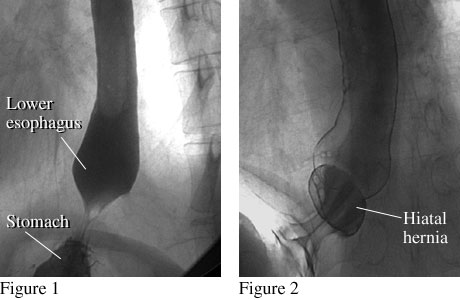

X-ray images after a barium swallow showing a normal esophagus and an esophagus with a hiatal hernia

Courtesy of Intermountain Medical Imaging, Boise, Idaho. All rights reserved.

Figure 1 shows the lower end of a normal esophagus with a smooth connection between the lower esophagus and stomach. Figure 2 shows the lower end of the esophagus with a small hiatal hernia, which occurs when a small portion of the stomach pushes up into the chest.